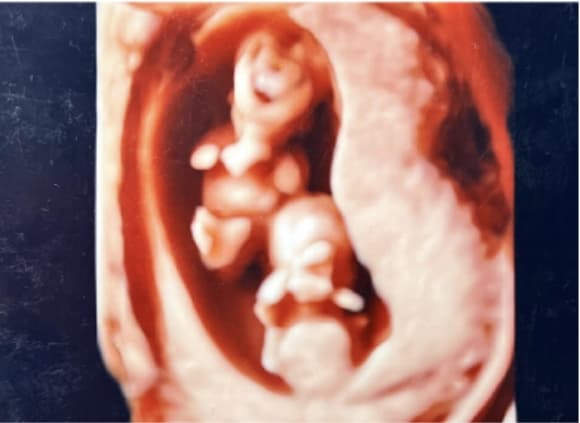

臍帯の首への券絡3回(3D血管エコー)

4D胎児エコー写真

4Dエコー外来

• 妊婦健診の中でいつでもご希望の時に、お腹の中の赤ちゃんの状態を立体的に、そして動きまでリアルにご覧いただける超音波技術を用いた4Dエコー外来が受診できます。

• お腹の中のお子さまの様子を鮮明にご覧いただくことが可能です。(希望者のみ:2,160円/回)

※当日の胎児の向きや、姿勢によって必ずしも顔がはっきり見られるとは限らないため、費用は見えたときのみいただいております。

一卵生双胎